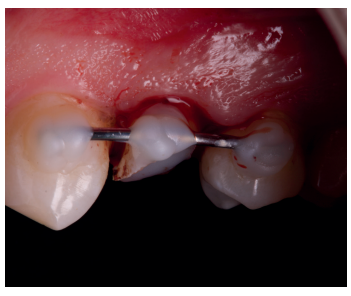

Tras la anestesia local con articaína al 4% y epinefrina 1:100.000 (Ultracain®, Laboratorios Normon, Madrid, España) del nervio alveolar superior y nervio palatino posterior, las fibras gingivales fueron separadas con uso de bisturí y periostotomos. Para la tracción del diente se realizaron movimientos de rotación, utilizando únicamente fórceps de raíces, hasta la reposición del diente en la posición deseada. Así, sujetándolo desde la posición más coronal y utilizando una gasa estéril, aunque no siempre es posible, se evita dañar la superficie radicular. En condiciones normales es posible que el diente solo precise movimiento coronal, como sucedió en este caso, pero si fuera necesario evaluar la integridad del diente o realizar una apicectomía, el odontólogo podría proceder a su exodoncia, examen con magnificación y posterior reimplante10. En este paso se hará aún más importante el uso de gasas estériles húmedas, el respeto por la superficie radicular y la rapidez en el procedimiento, siempre menor a 15 minutos14-16.

Una vez se hubo posicionado el diente 2 mm supragingival, se procedió a la ferulización con alambre de acero a los dientes adyacentes (Figuras 3 y 4) y la eliminación de cualquier tipo de oclusión, utilizando topes oclusales en los segundos molares inferiores. La ferulización se mantuvo durante dos semanas, coincidiendo con el momento de la endodoncia (Figura 5). El paciente fue citado para las revisiones periódicas y posteriormente para la rehabilitación del diente, una vez hubieron concurrido 6 semanas desde la extrusión, en las que se haya obtenido una cicatrización de los tejidos de soporte supracrestales10. En este momento, tras comprobar signos clínicos, periodontales y radiográficos saludables, se citó al paciente para el tallado y la confección mediante flujo digital (Cerec® System) de una endocorona de disilicato de litio (e.max®, Ivoclar Vivadent). El acondicionamiento de la corona se realizó con ácido fluorhídrico y silano, y para la cementación se utilizó cemento de resina (Calibra®, Dentsply Sirona).

adyacentes, tras la extrusión quirúrgica.